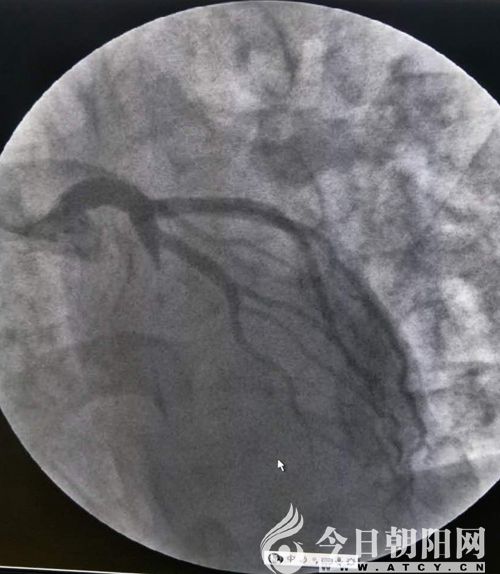

鄭某術(shù)后

兩名患者均屬于危急情況,相比之下,患者鄭某更重一些。單爽立即為鄭某實施手術(shù),術(shù)中見冠脈前降支支架內(nèi)100%狹窄,回旋支80%狹窄,血管內(nèi)布滿新發(fā)血栓,操作難度非常大。在導(dǎo)絲和球囊艱難通過后,依次進(jìn)行預(yù)擴(kuò)球囊及后擴(kuò)球囊于支架內(nèi)擴(kuò)張,前降支恢復(fù)三級血流,患者癥狀立即緩解。由于120急救中心在接診患者過程中,及時予以診斷,并開通綠色通道、免費心梗“一包藥”口服、建立左手靜脈通路等及時正確的處置,為患者的救治贏得了時間。